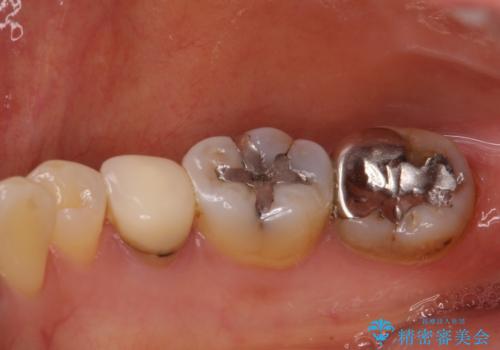

- 目立つ銀歯を気にして来院された患者様です。

奥歯を中心に銀歯が多く装着されており、一部の歯は咬合時に痛みを感じている状態でした。

必要な歯に根管治療を行い、オールセラミッククラウンにて補綴治療を行うこととしました。